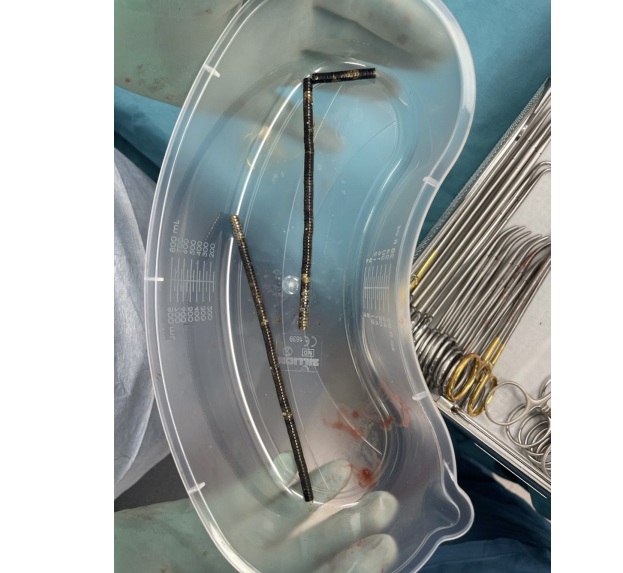

"Hij gaf aan dat hij ongeveer een week daarvoor ongeveer 80 tot 100 krachtige (neodymium)magneten van 5x2 millimeter had ingenomen", is te lezen in een rapport van artsen in het New Zealand Medical Journal. Uit de publicatie wordt niet duidelijk wanneer de jongen precies in het ziekenhuis werd opgenomen.

De chirurgen verwijderden het dode weefsel in de darmen van de jongen samen met de magneten, waarna hij na 8 dagen weer naar huis kon.